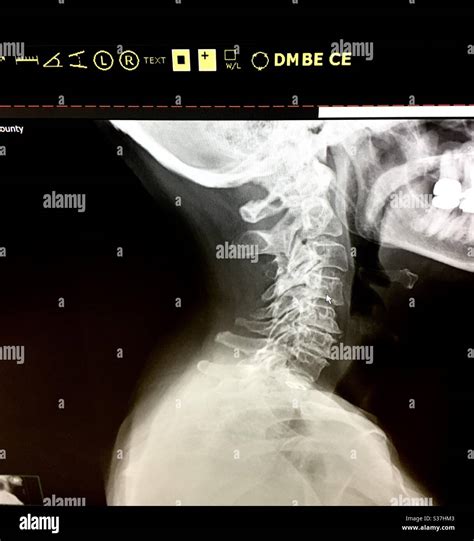

• Imaging Tests: X-rays, MRI, or CT scans to visualize the bones and soft tissues in the neck.